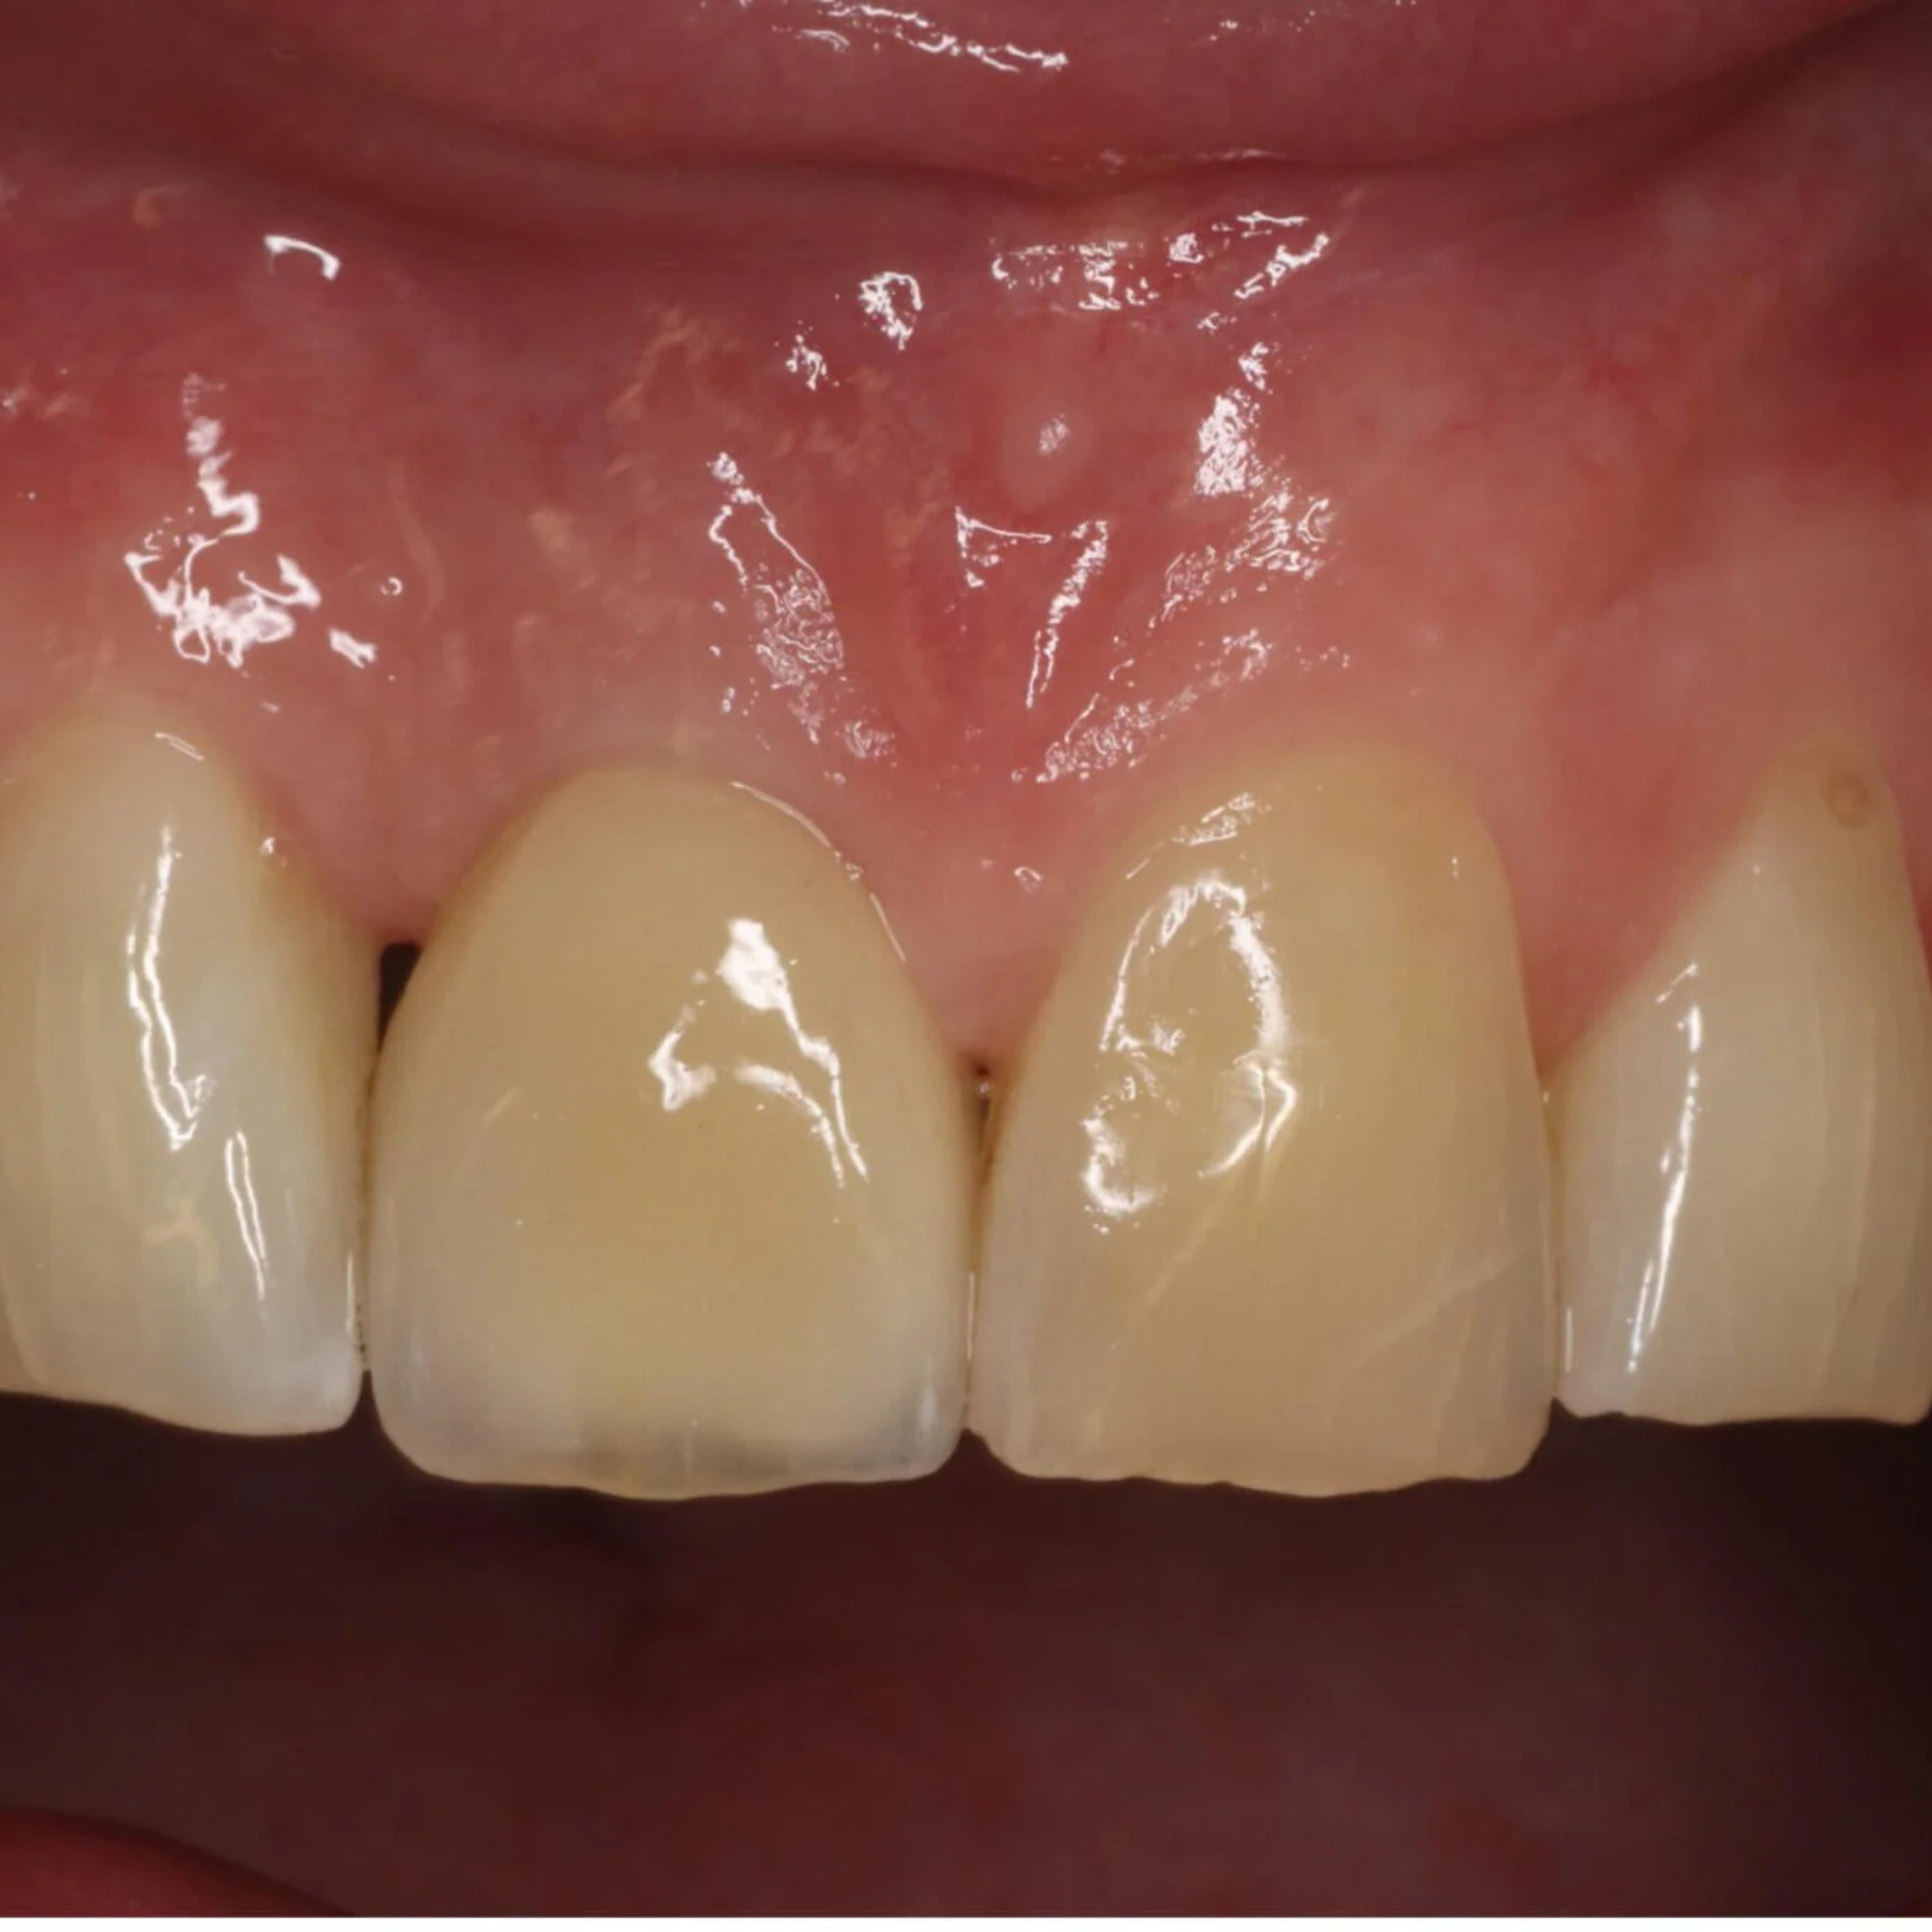

Implant Placement and Simultaneous Bone Grafting in the Aesthetic Zone